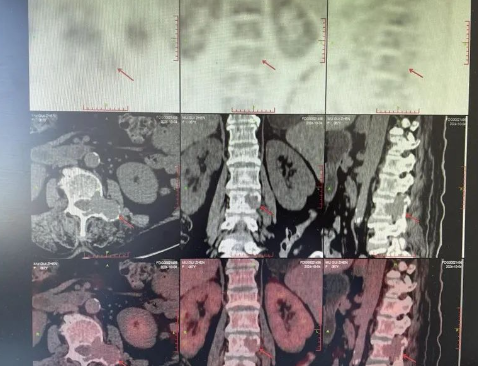

品質(zhì)國文丨追蹤腫瘤的“高精雷達(dá)”-PET/CT

PET/CT,被譽(yù)為腫瘤病灶追蹤的“高精雷達(dá)”、“生命衛(wèi)士”,作為健康體檢的高端手段之一,其優(yōu)勢(shì)在于既可顯示人體組織臟器的精確解剖圖像又能同時(shí)顯示人體組織、細(xì)胞的代謝功能圖像。 閱讀量:1355